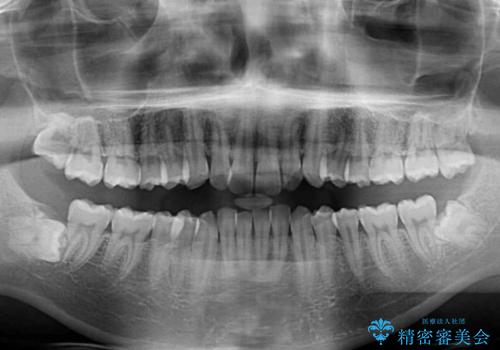

- 上下前歯のデコボコを気にして来院された患者様です。

全体的に叢生は軽度であったため、インビザラインにて矯正治療を行うこととしました。

デコボコの改善はもちろん、下顎前歯が隠れてしまうディープバイトも一緒に改善することができ、奥歯への負担を軽減することができました。